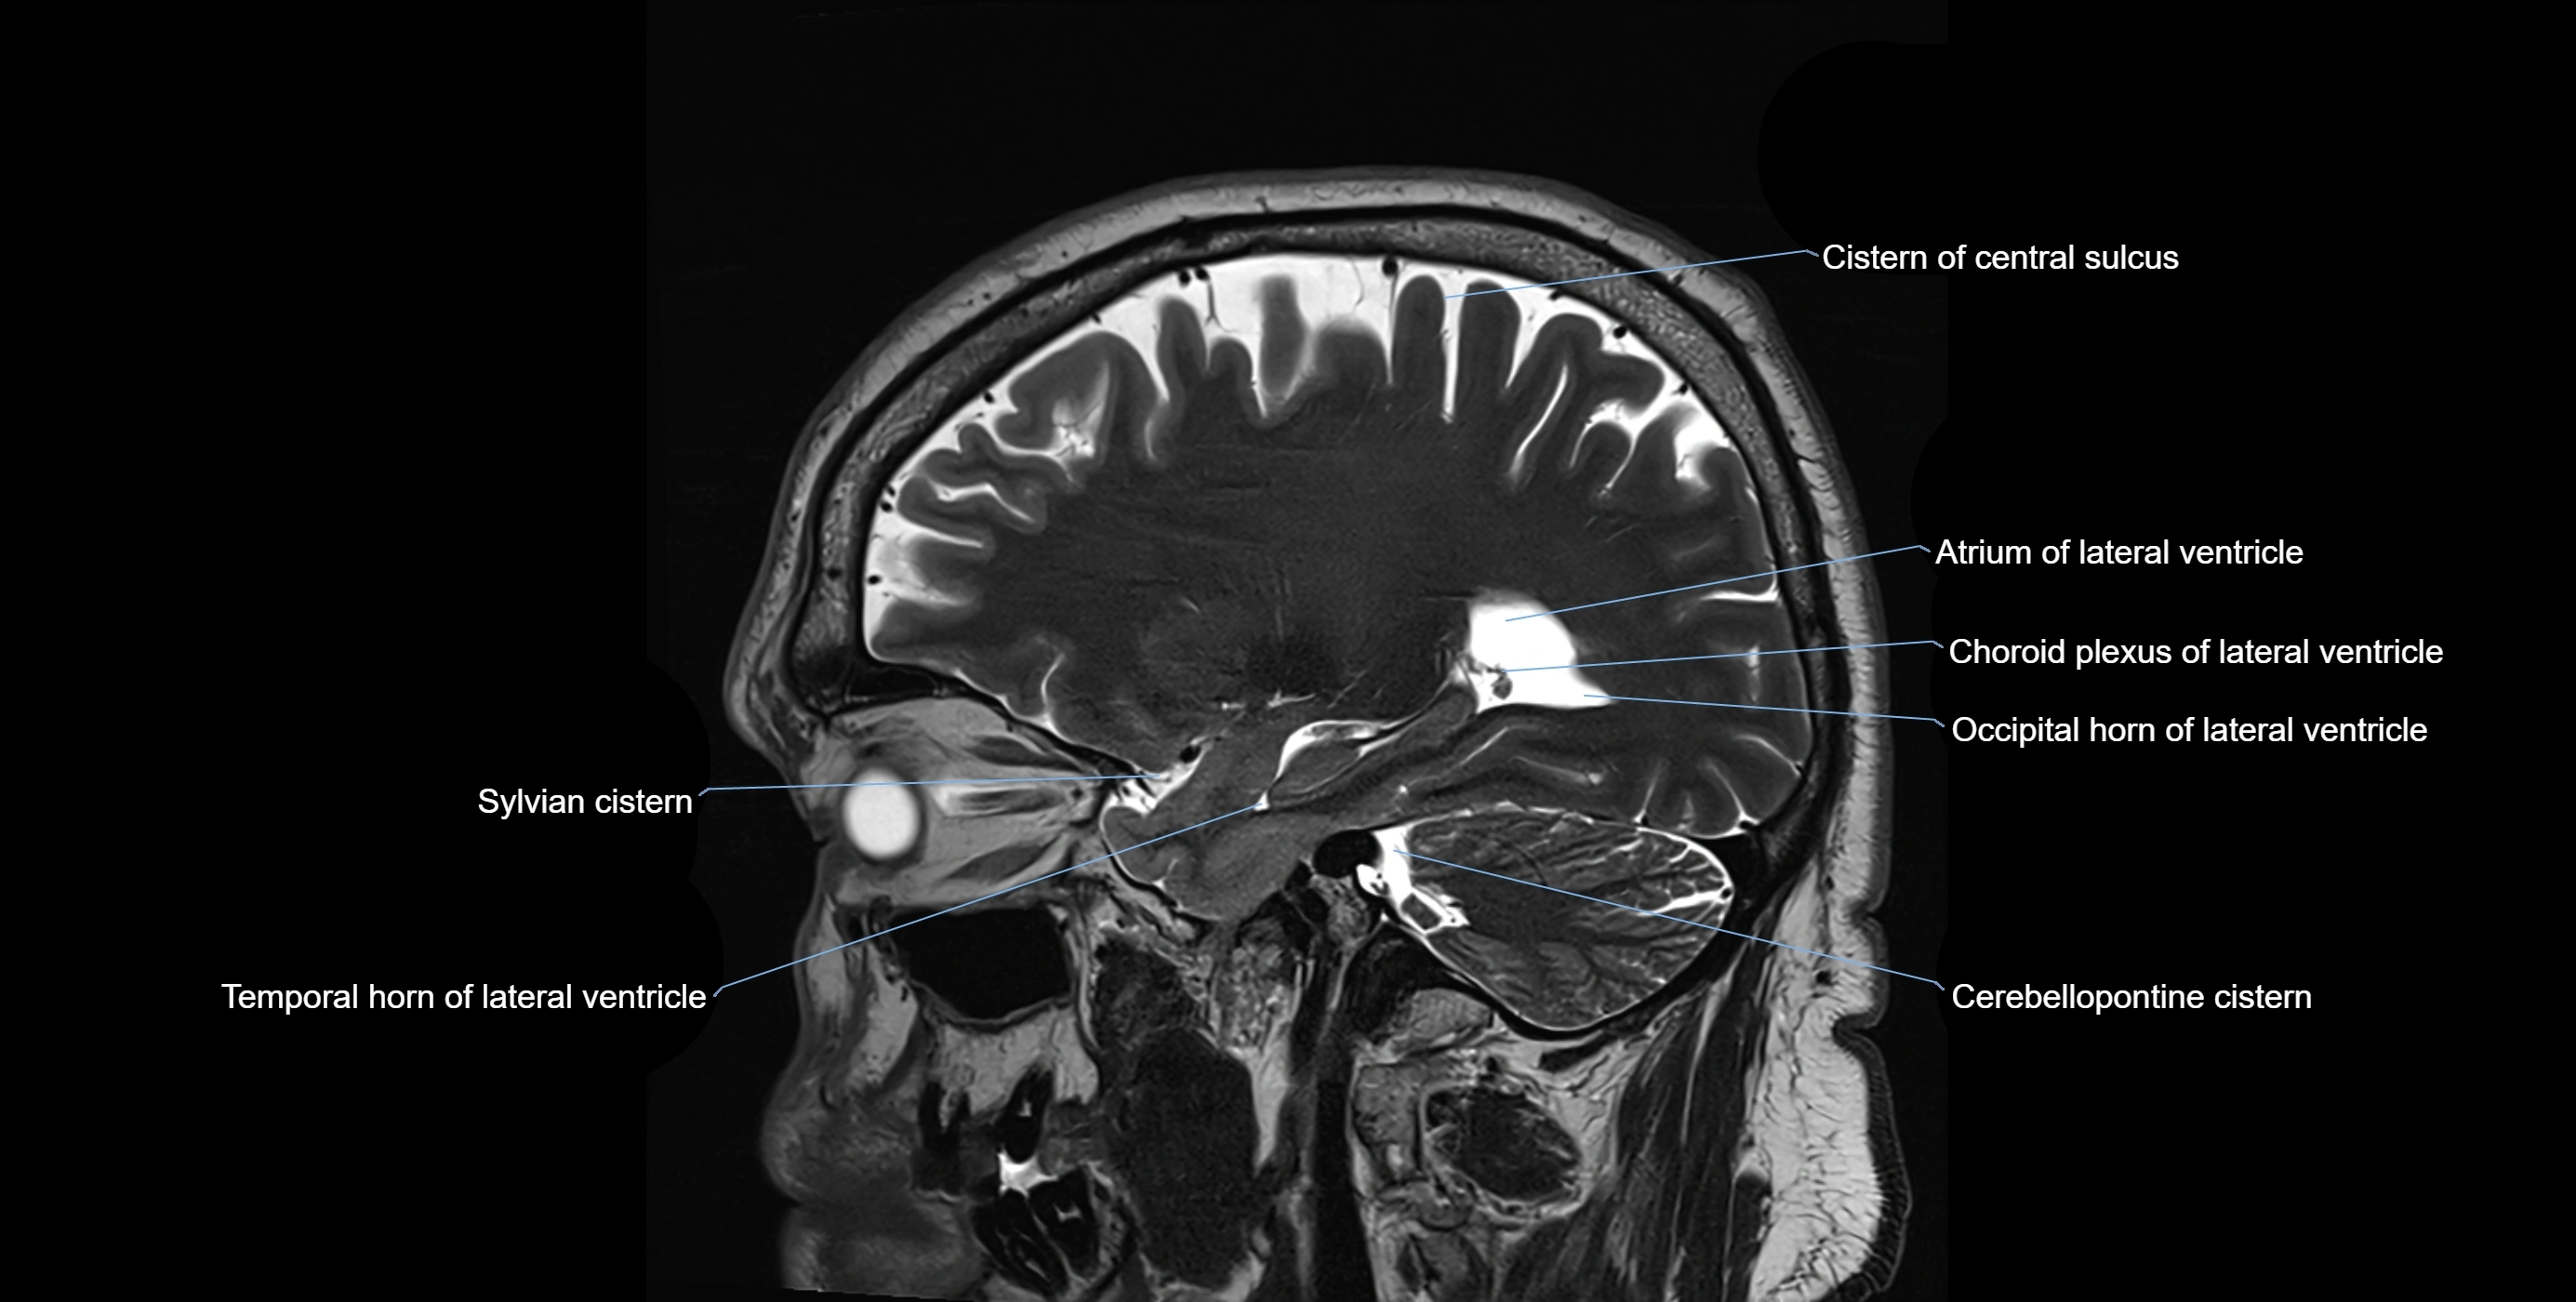

MRI images

image